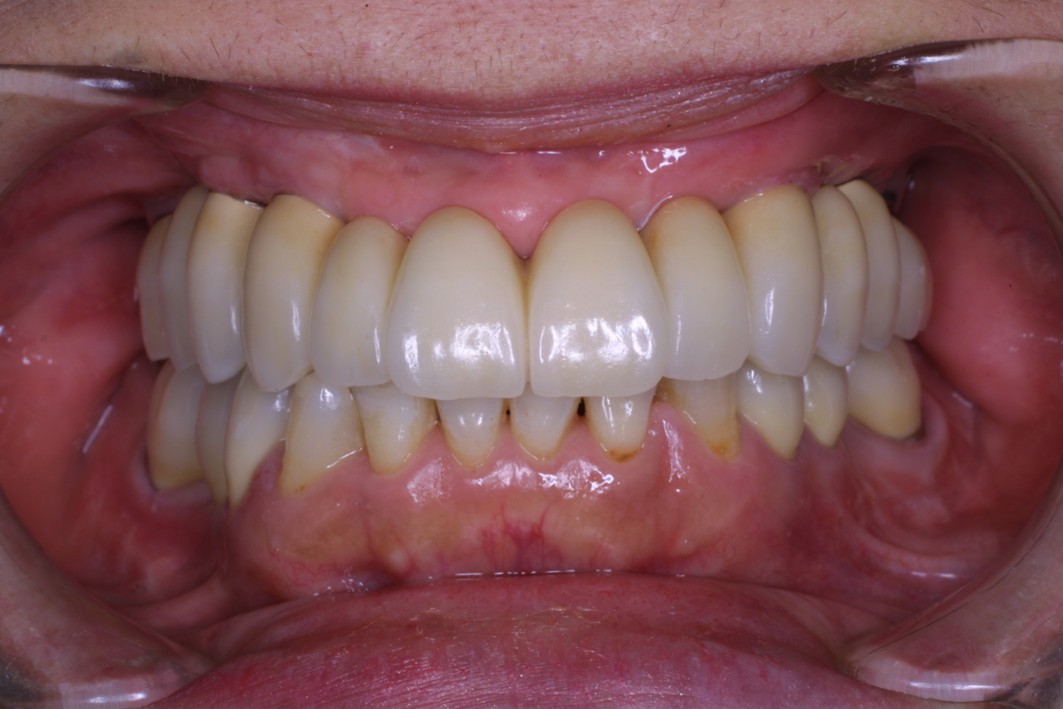

だからこそ、今悩んでいる患者さんにお伝えしたいことがあります。たとえ歯がボロボロの状態であっても、適切な歯科治療を受けることで、美しく機能的な歯を取り戻すことは十分に可能です。